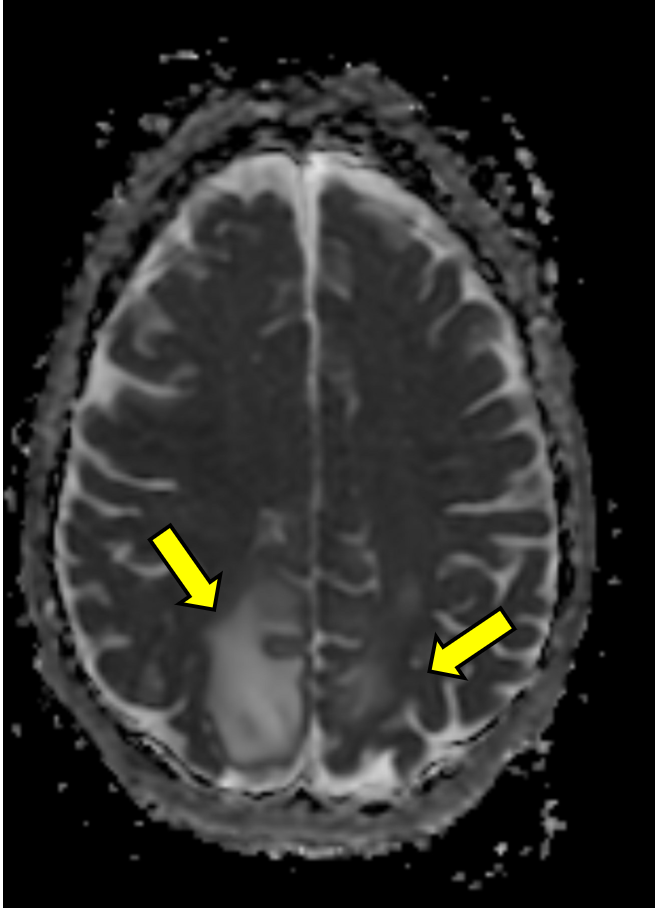

A few hours after admission she ultimately eloped during shift change. She returned to the same ED the next day after being found unresponsive outside again, was given Narcan en route as well as in the ED for bradypnea, and ultimately started on a naloxone drip, though she remained saturating well on room air. The initial temperature was 97.8°F and the initial BP was 121/83. Repeat head CT demonstrated the same vasogenic edema as seen previously (see Figure 1B). The patient was admitted again and remained normotensive. MRI with and without contrast demonstrated expansile T2/FLAIR hyperintense signal in the posterior frontal and parietal lobes, favored to be PRES (see Figure 1C and D).

Figure 1: Computed Tomography and Magnetic Resonance Imaging Demonstrating Posterior Reversible Encephalopathy Syndrome (PRES) Figure Caption: Initial (A) and next-day (B) CT imaging of concerning for PRES, with bilateral parietal vasogenic edema noted. MRI demonstrated expansile T2/FLAIR hyperintense signal in the posterior frontal and parietal lobes, favored to be PRES (C and D). Arrows correspond to areas of interest.

Initial (A) and next-day (B) CT imaging of concerning for PRES, with bilateral parietal vasogenic edema noted. MRI demonstrated expansile T2/FLAIR hyperintense signal in the posterior frontal and parietal lobes, favored to be PRES (C and D). Arrows correspond to areas of interest.